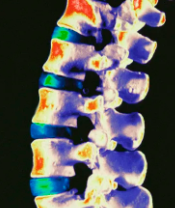

2016 SOSORT指南:在成长期间特发性脊柱侧凸的骨科和康复治疗

国际脊柱侧凸整形外科和康复治疗协会发布的治疗指南,从2005年开始,并不断修订和增加。目标是帮助所有的专业人员以及病患者,以循证观点为基础,获取脊柱侧弯保守疗法的真实信息。每年举行一次年会。